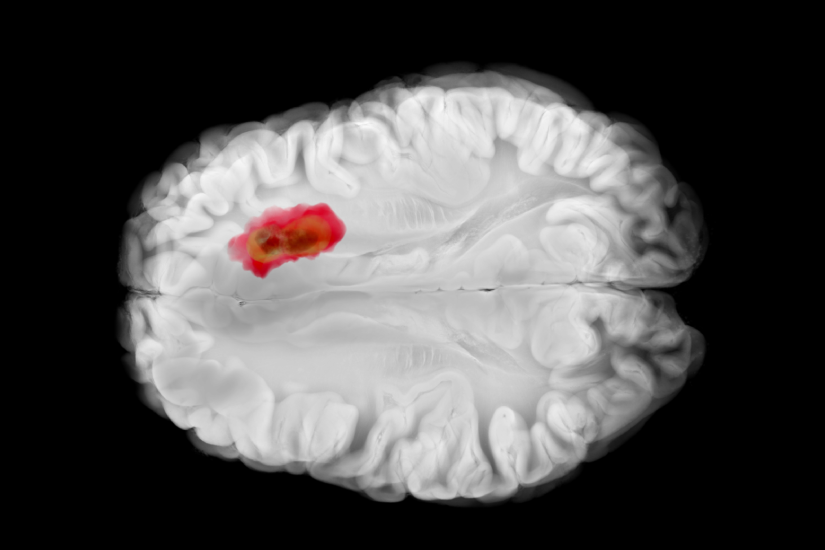

Glioblastomul, cunoscut istoric și ca glioblastom multiform (GBM), este cea mai comună și cea mai agresivă formă de tumoră cerebrală primară (care își are originea în creier) la adulți. Este un tip de astrocitom (o tumoră care provine din celulele gliale numite astrocite) și este clasificat de Organizația Mondială a Sănătății (OMS) ca tumoră de grad 4, cel mai înalt grad de malignitate.

Agresivitatea sa este cauzată de faptul că celulele sale se divid foarte rapid și sunt susținute de o rețea extinsă de vase de sânge (angiogeneză). De asemenea, glioblastomul are o tendință majoră de a se infiltra adânc în țesutul cerebral sănătos din jur, ceea ce face îndepărtarea chirurgicală completă extrem de dificilă sau imposibilă.

- Imagistică prin rezonanță magnetică (RMN): Este metoda de elecție. RMN-ul cerebral cu substanță de contrast (gadoliniu) este esențial. În cazul glioblastomului, imaginile arată de obicei o masă neregulată, care captează intens contrastul la periferie (sub formă de inel) și are un centru necrotic.

- Biopsia (analiza țesutului): Este obligatorie pentru confirmare. Un neurochirurg prelevează o mostră de țesut (fie printr-o biopsie stereotactică, fie în timpul operației de îndepărtare a tumorii). Țesutul este analizat de un medic anatomopatolog pentru a confirma gradul 4 și pentru a efectua teste moleculare vitale (ex. statusul promotorului MGMT, statusul IDH).